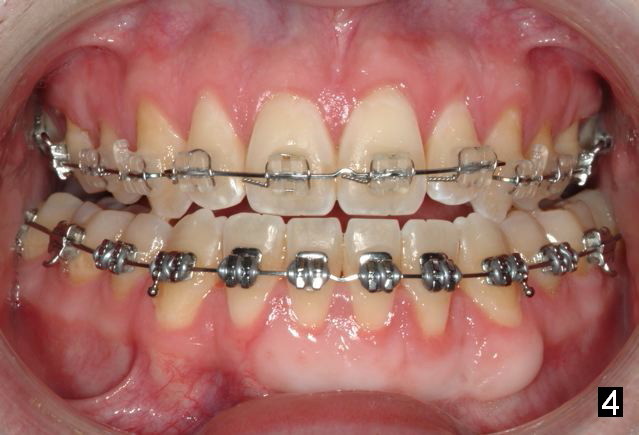

Initial bonding on 08/04/2014 (Fig.1-3); follow up appointments (09/20/2014 (Fig.4,5); 11/11/2014 (Fig.6,7), prepared for maxillary segmental surgery to expand, advance, and level.

I routinely start off with a round NiTi AW, like .014 in the .018 slot, then to .016 and up to 16X22 NiTi. Then I go to rectangular SS.  I segmented the AW to facilitate the surgery.

What is advantage to segment AW initially (in the 1st appointment of bonding, Fig.1,2)?

Avoids compensating teeth and building in instability in a surgery case.

A continuous AW would align AND 'level'. The rule is never move teeth before surgery in a direction they will be corrected at the time of surgery. This concept we may need to talk in person.